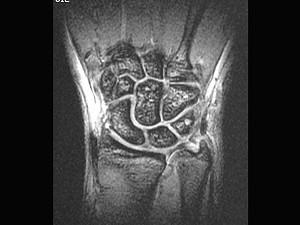

问题 男,27 岁,外伤后尺腕部疼痛,结合图像,最可能的诊断是 ( )

选项 A、尺骨骨折 B、三角纤维软骨复合体裂伤 C、三角骨无菌性坏死 D、三角骨骨折 E、未见异常

答案 B